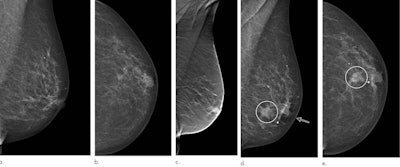

Images in a 72-year-old woman who was diagnosed with a 13-mm lymph node-negative invasive lobular carcinoma luminal B-line human epidermal growth factor receptor 2 breast cancer 18 months after a screening negative for cancer in the Malmö Breast Tomosynthesis Screening Trial. (a) Mediolateral oblique and (b) craniocaudal digital mammography images at screening. The slight retraction of the nipple was unchanged compared with previous digital mammography screening images. (c) Digital breast tomosynthesis at screening. Digital mammography of (d) mediolateral oblique and (e) craniocaudal views at diagnosis, small marker at lump location. Increased nipple retraction (arrow) and central mass (circle on d and e). Images and caption courtesy of Radiology.The group also examined the impact of DBT on interval cancers by age group. Women under 55 years old in the trial had an interval cancer rate of 1.3 per 1,000, compared with the 2.6 per 1,000 seen in the control group. Meanwhile, women over 55 years old in the trial had an interval cancer rate of 1.8 per 1,000, compared with the 3 per 1,000 seen in the control group. However, these differences were not statistically significant.